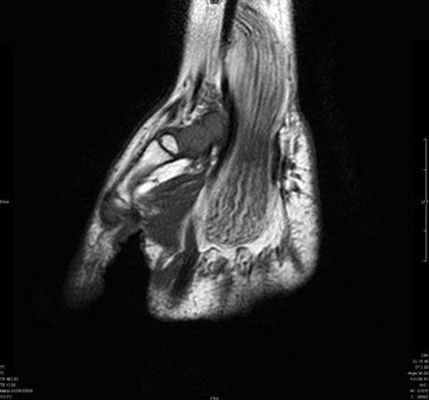

Результат МРТ правого лучезапястного сустава (рис. 2), подтвердил клиническое предположение о повреждении ладьевидно-полулунной связки, который заключался в нарушении целостности структуры связки. Также были выявлены признаки асептического некроза ладьевидной кости в стадии отека костной ткани.

Рис. 2. МРТ-исследование правого лучезапястного сустава. Получены протон взвешенные изображения с подавлением сигнала от жировой ткани (PD FAT SAT) в аксиальной, сагиттальной и фронтальной плоскостях, Т1 взвешенные изображения во фронтальной плоскости. На полученных сканах определяется: 1 – увеличение ладьевидно-полулунного сустава вдвое по сравнению с соседними; 2 – вдоль оси ладьевидной кости отмечается скопление жидкости, что можно расценить, как продольный перелом ладьевидной кости, либо отек костной ткани